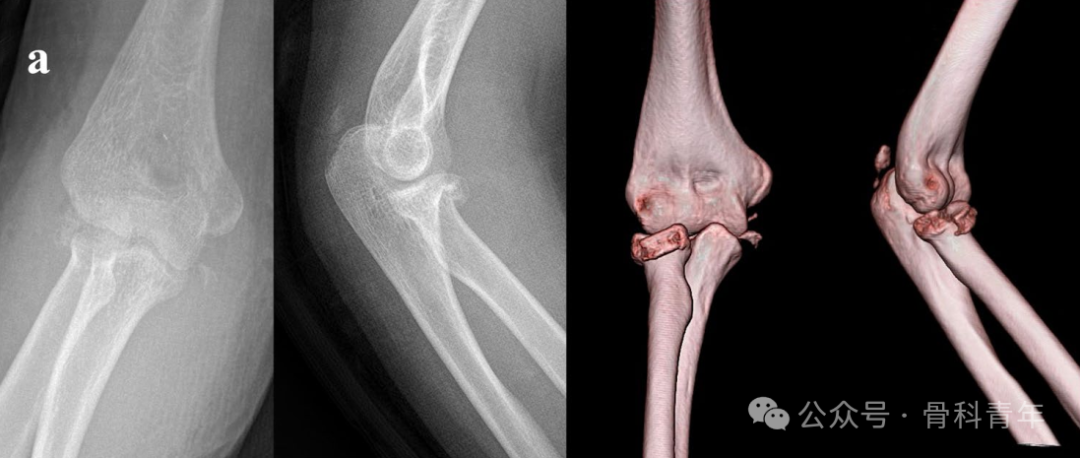

病例3:后孟氏骨折,桡骨头骨折采用2枚可吸收螺钉固定。